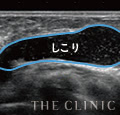

失敗例2

30歳・3年前に注入

左胸のみ、しこりができてしまったようです。最新エコーで診察したところ、最大5cmもの大きなしこりであるため、豊胸施術時に吸収されないほどの大きな塊で注入されたことが原因でしょう。ヒアルロン酸は吸収・消失される程度のサイズで注入することが重要です。